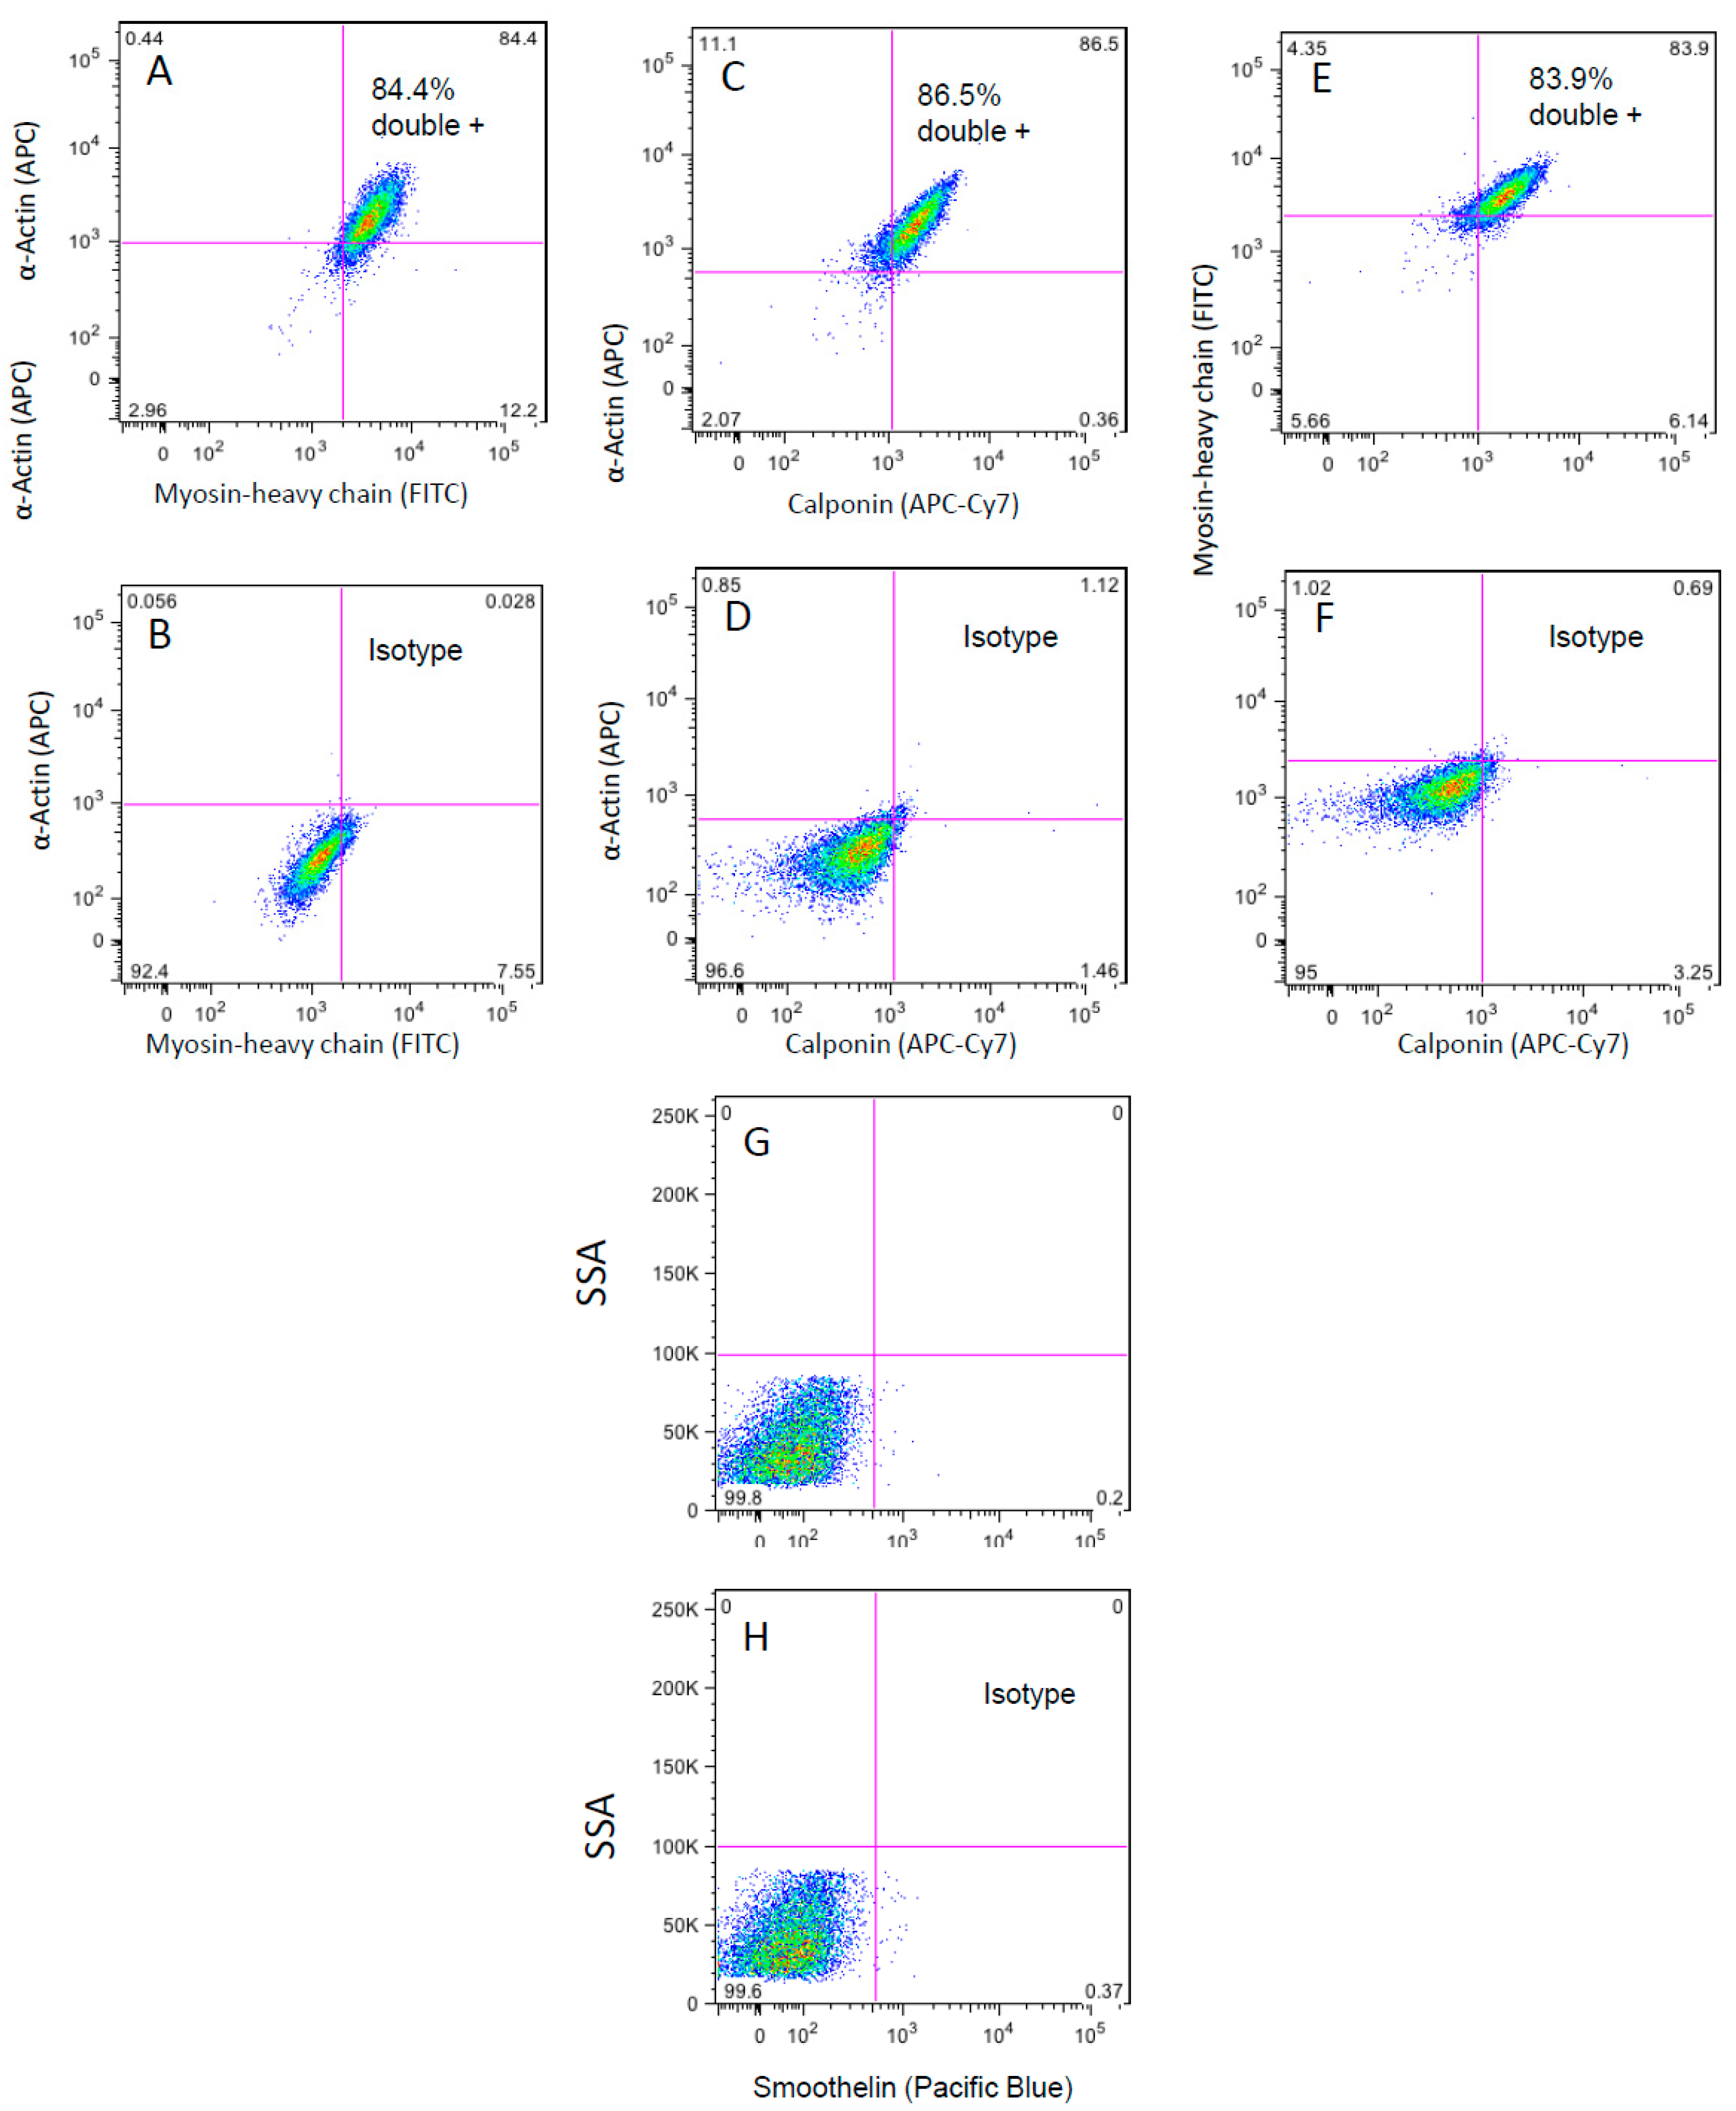

3.3. Flow Cytometry Analysis of the WG-59 Cell Line